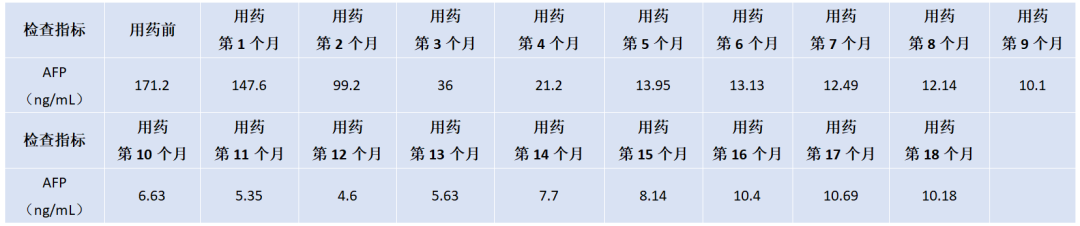

2. TNF-α与IFN-γ变化

用药后TNF-α下降明显,IFN-γ呈上升趋势,详见图2。

图2. TNF-α和IFN-γ水平变化

淫羊藿素软胶囊属于国家中药1.2类新药,是从传统中药淫羊藿中提取、分离、纯化、酶解而来的单体小分子药物。此药的特点是起效缓慢,但是起效后有效时间长,通过下调IL-6、IL-8、TNF-α,上调IFN-γ,改变免疫而达到杀伤肿瘤的作用。2022年CSCO原发性肝癌指南中,淫羊藿素软胶囊用于晚期肝癌一线治疗获得Ⅰ级专家推荐,也是唯一的Child-Pugh评分≤7分或>7分均获推荐的一线方案(IB类证据)。

从作用机制上看,淫羊藿素单体小分子属于免疫调节抗肿瘤药物,可通过直接结合并作用于在免疫系统和癌症发生机理中起重要作用的TLRINF-kB信号传导通道中的靶点蛋白MyD88和IKKα,调控以IL-6/JAK/STAT3为主的炎症和免疫调节信号通路,从而调节肿瘤细胞、肿瘤免疫微环境中不同免疫细胞的多个生物学功能,包括促进肿瘤细胞凋亡,抑制肿瘤细胞生长,抑制炎症因子IL-6、IL-8、IL-10、TNF-α的表达,以及抑制免疫检查点PD-L1的表达。因此,淫羊藿素能够抑制肿瘤细胞生长,同时降低炎症因子和免疫抑制来促进免疫功能的恢复,改善肿瘤炎症免疫微环境。